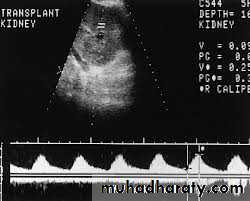

Doppler study of renal artery.

Vascular imaging is required to diagnose renovascular disease.